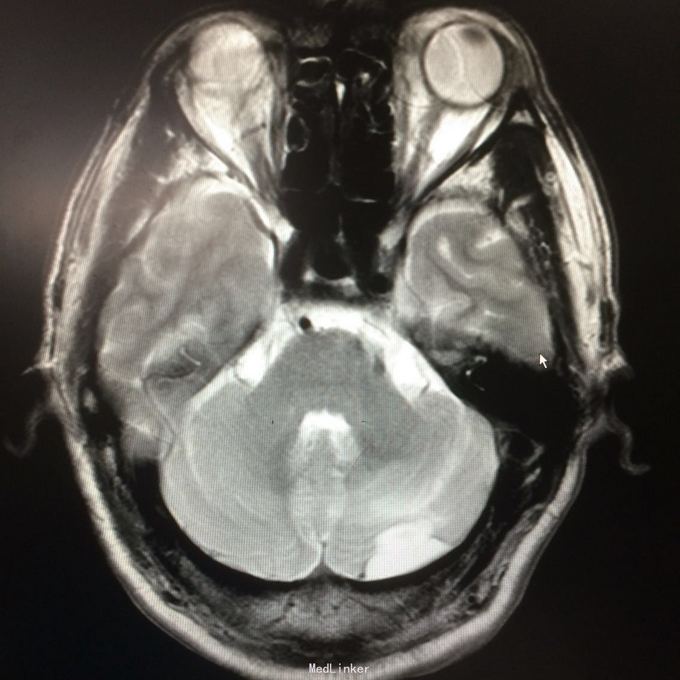

主诉:头晕头痛2年 病史:2年前无明显诱因出现头痛,呈刺痛,程度较重,伴头晕、天旋地转感,1年前查头颅MR提示:左侧小脑半数囊性病变,考虑血管母细胞瘤

查体:神志清楚,病理证阴性 辅助检查:头颅MR提示左侧小脑半数后部囊状占位灶,考虑良性病变。

诊断:左侧小脑血管母细胞瘤 处理:行左侧小脑占位病变切除术,术后病理提示:符合血管母细胞瘤。